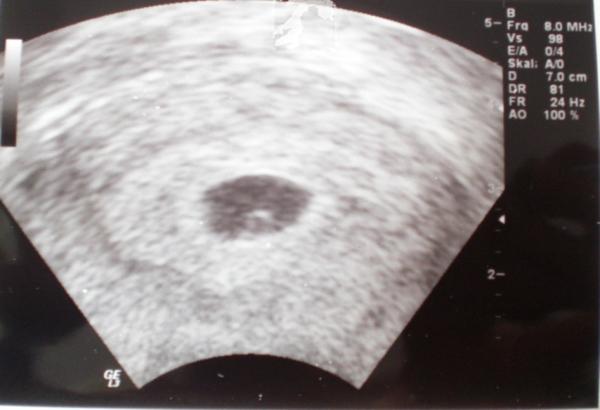

Schau mal auf mein US-Bilod von damals, da war ich auch SSW 6 (5+5)

Hallo Ihr Lieben, war heute das erste Mal zur Untersuchung beim FA. Sie hat mich über einige Dinge aufgeklärt, Blut abgenommen und nen Ultrschall gemacht und naja..da war ein miniminimini Punkt und erennen konnte man noch gar nichts. Hab sie gefragt ob ma denn nun schon eine eilieterss ausschließen kann...konnte sie nicht! Ist das normal in der 6. Woche? (5+4)? LG maja